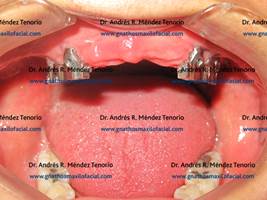

Foto clínica diente ausente

| Rehabilitación terminada | |

| Antes y después de rehabilitación de premolar y molar inferiores izquierdos con implantes | |